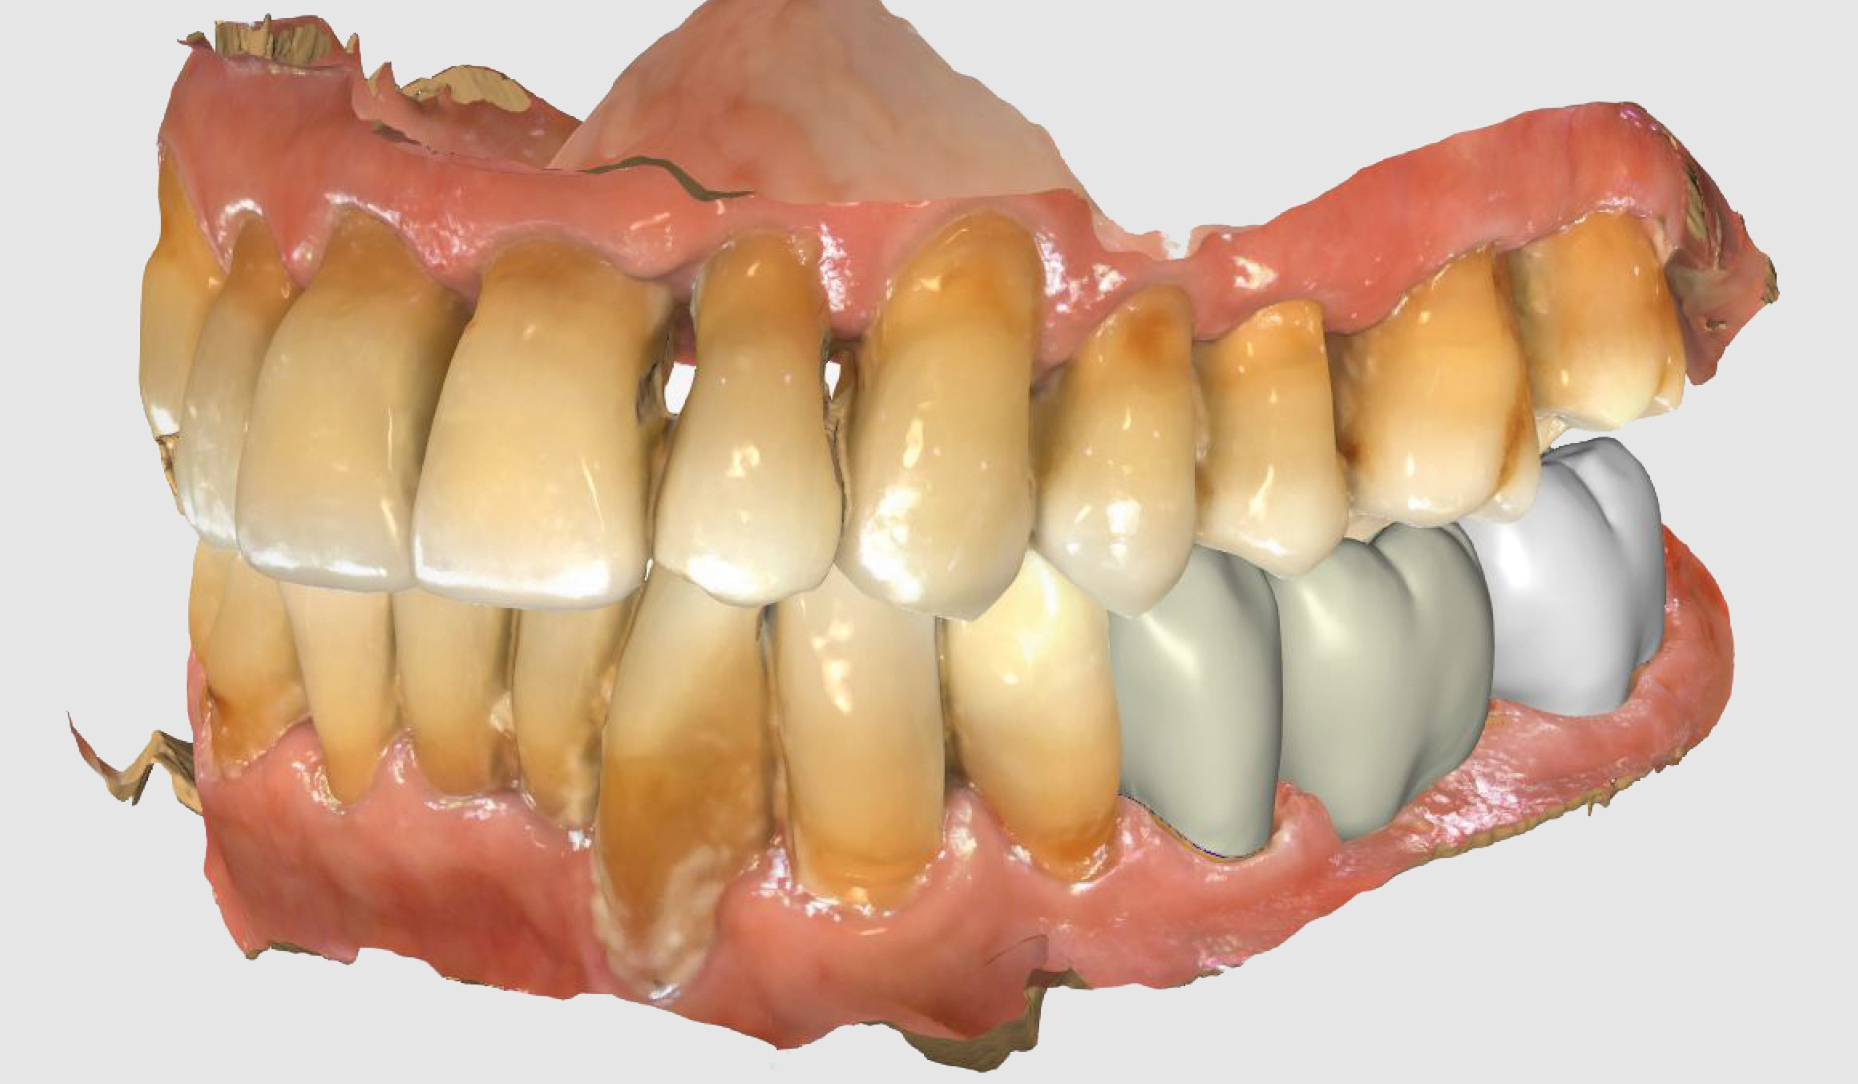

Ryc. 4. Projekt mostu...

Ryc. 5. ...widok powierzchni żującej w oprogramowaniu CEREC.